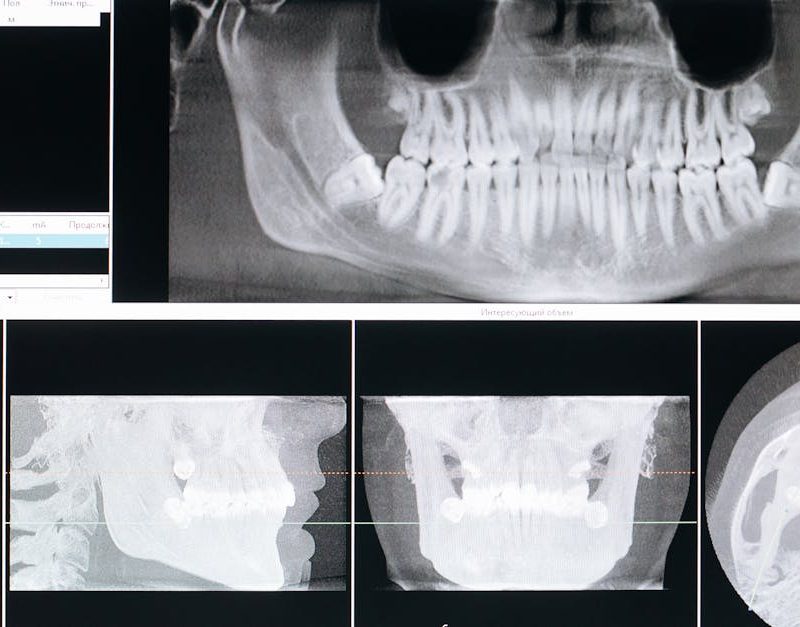

Corachán Maxilofacial